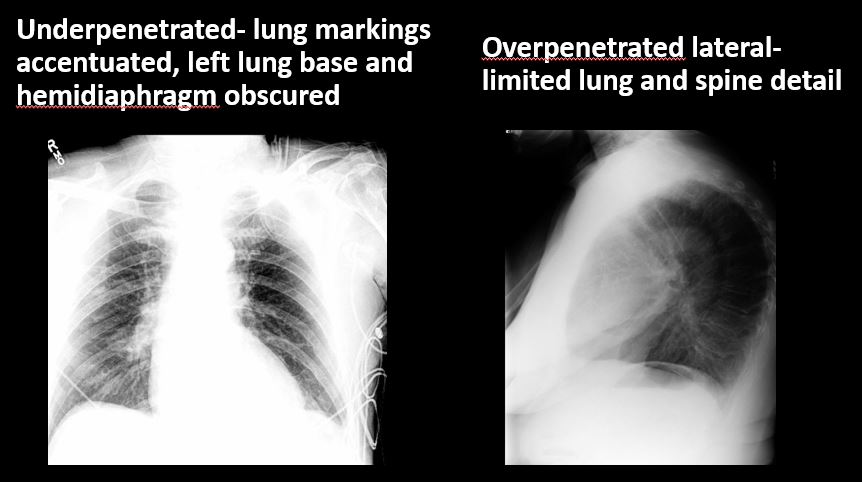

The exam is expiratory, rotated, over or under penetrated, or limited by overlying structures or soft tissues, body habitus, patient positioning, or motion. [Yes/No]